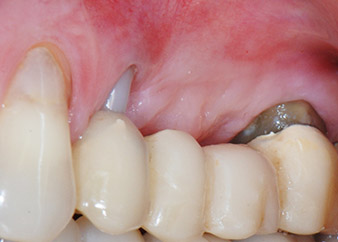

След един месец, в деня на операцията, болката и възпалението в зъб 24 е минимално, но подвижността в Miller class 2 е на лице. След отваряне на ламбата и почистването на периапикалната и перирадикуларната тъкани, обхватът на костния дефект стана очевиден (Фиг. 2 и 3).

тотална загуба на кост и захват

Фиг. 2 и 3: След повдигане на ламбото, един месец след ендодонтския преглед и прилагане на цялостна периодонтална терапия в цялата уста, букалният корен на зъб 24 разкри тотална загуба на кост и захват.